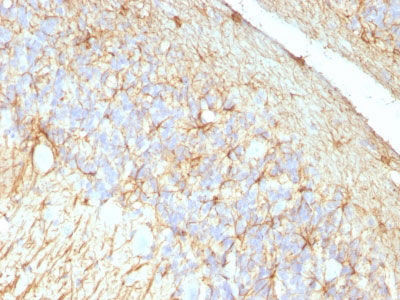

Formalin-fixed, paraffin-embedded human Cerebellum stained with GFAP Monoclonal Antibody (GA-5 + ASTRO/789).

Formalin-fixed, paraffin-embedded Rat Cerebellum stained with GFAP Monoclonal Antibody (GA-5 + ASTRO/789).

Formalin-fixed, paraffin-embedded human Schwanoma stained with GFAP Monoclonal Antibody (GA-5 + ASTRO/789). |

This MAb recognizes a protein of ~50kDa which is identified as Glial Fibrillary Acidic Protein (GFAP). It shows no cross-reaction with other intermediate filament proteins. GFAP is specifically found in astroglia. GFAP is a very popular marker for localizing benign astrocyte and neoplastic cells of glial origin in the central nervous system. Antibody to GFAP is useful in differentiating primary gliomas from metastatic lesions in the brain and for documenting astrocytic differentiation in tumors outside the CNS.

GFAP, a class-III intermediate filament, is a cell- specific marker that, during the development of the central nervous system, distinguishes astrocytes from other glial cells.